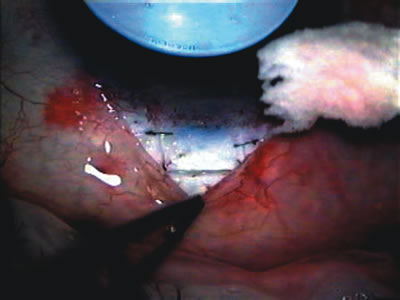

Fig. 4. Viscocanalostomy with deep sclerectomy and phacoemulsification. Nonpenetrating filtration procedures (NPFS) may be combined with phacoemulsification. Patients with mild disc damage and a history of limited topical drug therapy are the best candidates. Patients who require an IOP in the low teens are not good candidates for NPFS. By definition, NPFS is designed to lower IOP without penetrating into the anterior chamber, thereby avoiding the complications associated with trabeculectomy. Viscocanalostomy is intended to allow aqueous to percolate through a trabeculodescemetic membrane into a subscleral cavern created by the deep sclerectomy. The aqueous diffuses from the cavern into the dilated ostia of Schlemm's canal and into the episcleral venous plexus. A. Fashion a uniform 300-micron superficial scleral flap 1 mm into clear cornea. B. Construct a second 600-micron deep flap that facilitates the unroofing of Schlemm's canal, seen as the darker area. C. Use viscoelastic to dilate the ostia of Schlemm's canal. The major problem with viscocanalostomy is the eventual closure of the ostium decreasing flow to the episcleral plexus. D. Dissect the deep flap anteriorly into clear cornea creating the trabeculodescemetic membrane. This membrane is clearly seen between the scleral spur and the bend of the deep flap. The integrity of this membrane ensures the nonpenetrating portion of the surgery. Another problem with NPFS is the eventual fibrosis of this initially transparent membrane requiring goniopuncture. E. Deep sclerectomy gets its name from removal of the deep flap. Removal of this flap creates the potential subscleral space for accumulation of aqueous before it enters Schlemm's canal and exits the episcleral venous plexus. After removal of the deep flap, the superficial flap is sutured into place and conjunctiva closed. Approximately half of these procedures develop a shallow bleb.